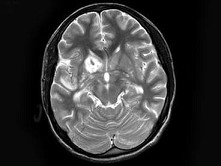

男,17岁,头痛呕吐,发热20天,脑膜刺激征阳性,MRI平扫及增强扫描,最可能的诊断是()

• A.结核性脑膜脑炎

• B.化脓性脑膜脑炎

• C.寄生虫感染

• D.颅内转移瘤